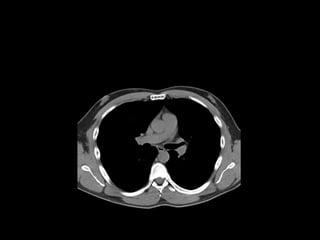

The document discusses the anatomy of the chest x-ray and CT scan by describing the lobes of the lungs and their locations. It also mentions the heart, mediastinum, hilum, and ribs. Several axial, coronal, and sagittal CT images are included with labels pointing out structures like the trachea, bronchi, lobes of the lungs, and fissures. In summary, the document provides an overview of lung and chest anatomy as seen on x-rays and CT scans through text descriptions and labeled medical images.